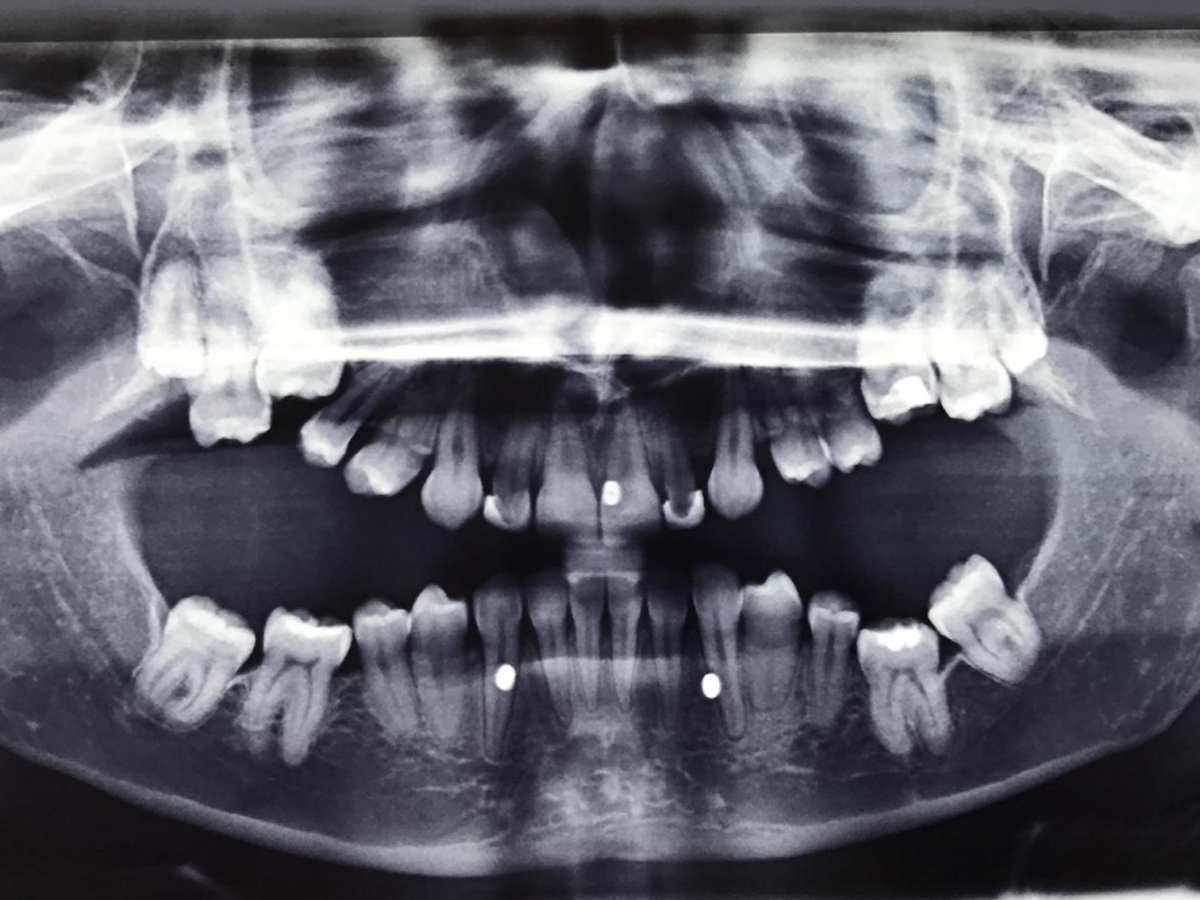

Hallöchen mein Name ist Michelle und ich bin 31 Jahre alt. Ich leide an dentaler Ankylose die bei mir genetisch bedingt ist, also schon mein ganzes Leben.

Das heißt, meine Zähne sind mit meinem Kieferknochen verwachsen und somit nicht durchgebrochen. Ich besitze keine richtigen Backenzähne und die Zähne im vorderen Bereich sind sehr klein und einige sind Zapfenzähne ( kleine Spitze Zähne).

Mit 13 Jahren fing meine Behandlung an, da ich nicht kauen konnte und immer nur auf den vorderen Zähnen rumknapperte.

Viele Zahnarztbesuche, Behandlungversuche und jahrelange Zahnspange halfen nicht viel, bis klar war da bewegt sich nichts und somit meine Erkrankung festgestellt wurde. Da war ich dann ungefähr 17.